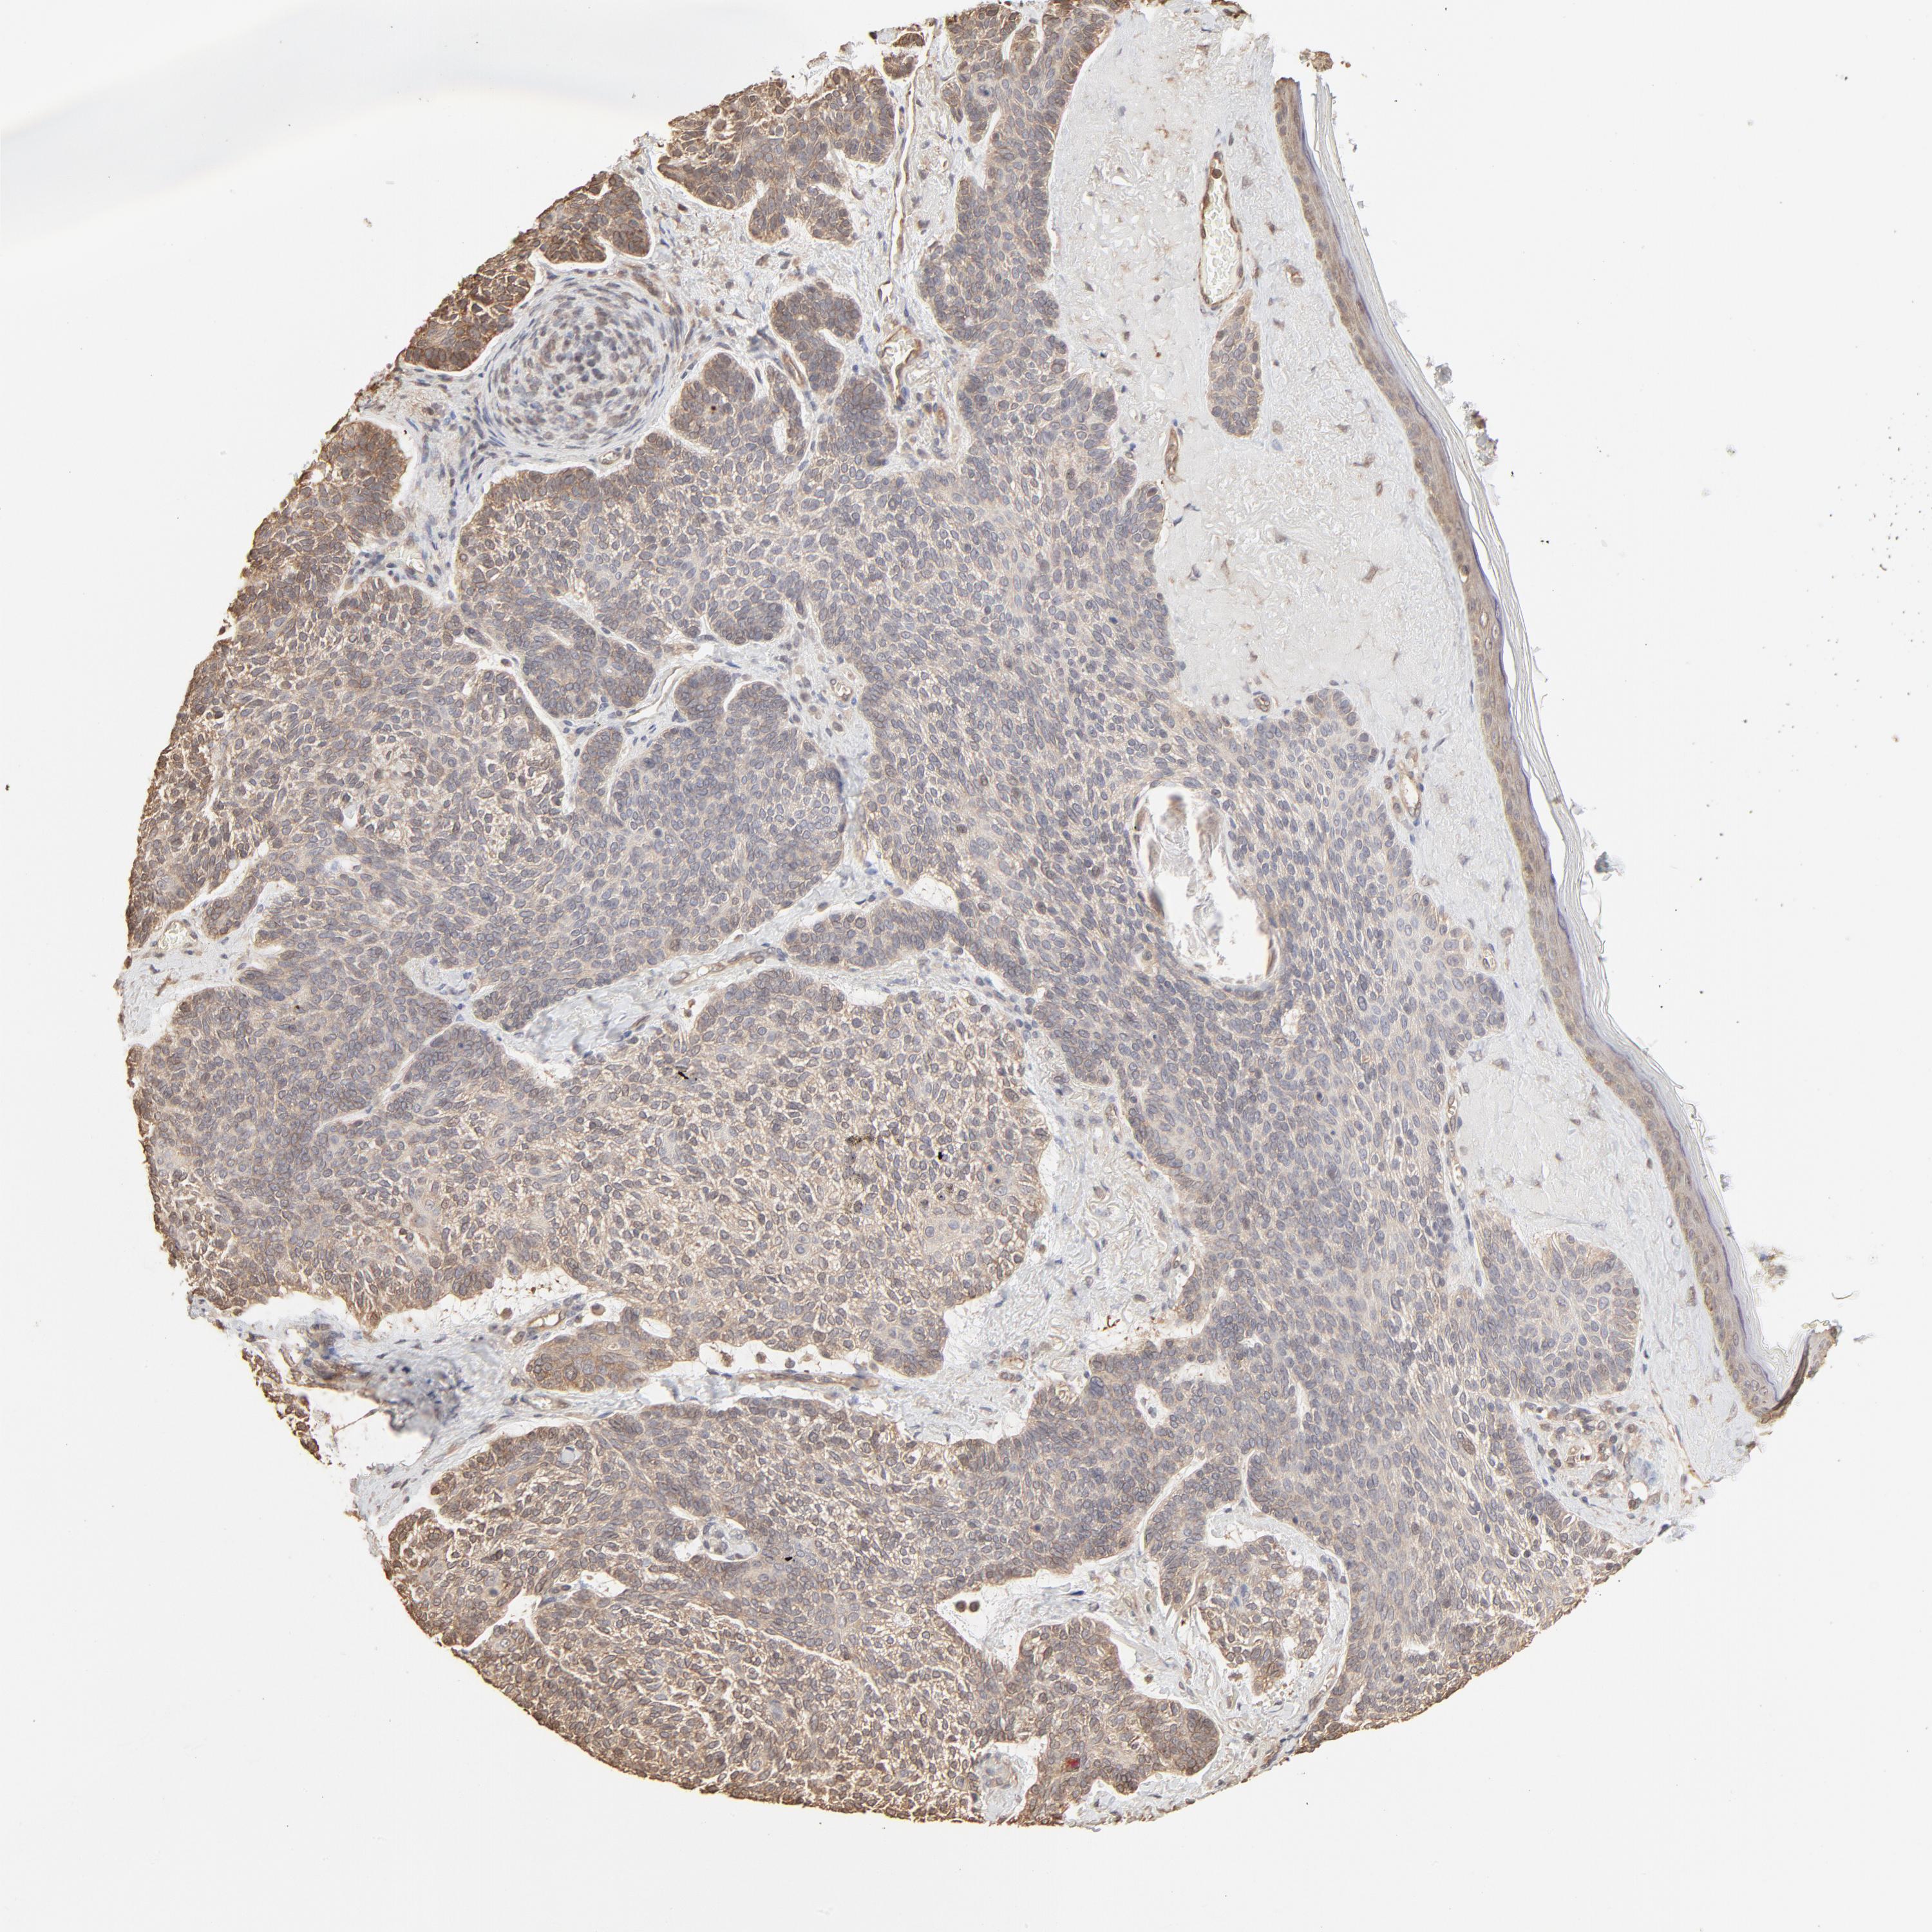

SKIN CANCER - Protein expressioni

A mouse-over function shows sample information and annotation data. Click on an image to view it in a full screen mode. Samples can be filtered based on level of antibody staining by selecting one or several of the following categories: high, medium, low and not detected. The assay and annotation is described here.

Antibody stainingi

Antibody staining in the annotated cell types in the current human tissue is reported as not detected, low, medium, or high, based on conventional immunohistochemistry profiling in selected tissues. This score is based on the combination of the staining intensity and fraction of stained cells.

Each image is clickable and will lead to virtual microscopy that enables deeper exploration of all samples and also displays staining intensity scores, fraction scores and subcellular localization as well as patient and tissue information for each sample.

Antibody HPA043236

Antibody CAB003848

Basal cell carcinoma

Squamous cell carcinoma, NOS